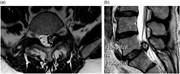

Spontaneous resolution of symptomatic lumbar synovial cyst

Priyank Sinha and others

Journal of Surgical Case Reports, Volume 2016, Issue 10, October 2016, rjw166, https://doi.org/10.1093/jscr/rjw166